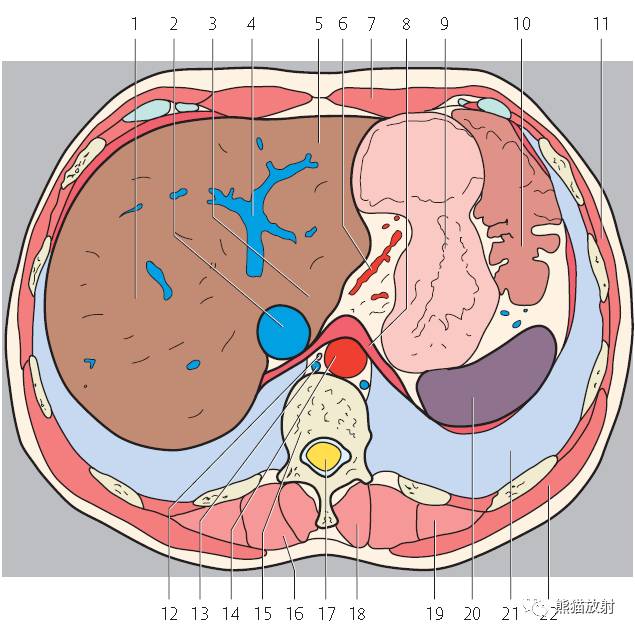

第二层

腹腔(粉色);腹膜后(黄色)

1、肝右叶;2、下腔静脉;3、肝尾状叶;4、肝门静脉;5、肝左叶;6、胃左动脉;7、腹直肌;8、膈肌;9、胃;10、结肠左曲;11、腹外斜肌;12、胸导管;13、奇静脉;14、腹主动脉;15;胸椎;16、最长肌;17、椎管和脊髓;18、棘肌;19、髂肋肌(胸段);20、脾脏;21、左肺;22、背阔肌;23、肋膈隐窝;24、右膈下隐窝;25、肝裸区;26、膈上淋巴结;27、肋间淋巴结;28、后纵隔;29、膈下淋巴结;30、左侧结肠旁沟。